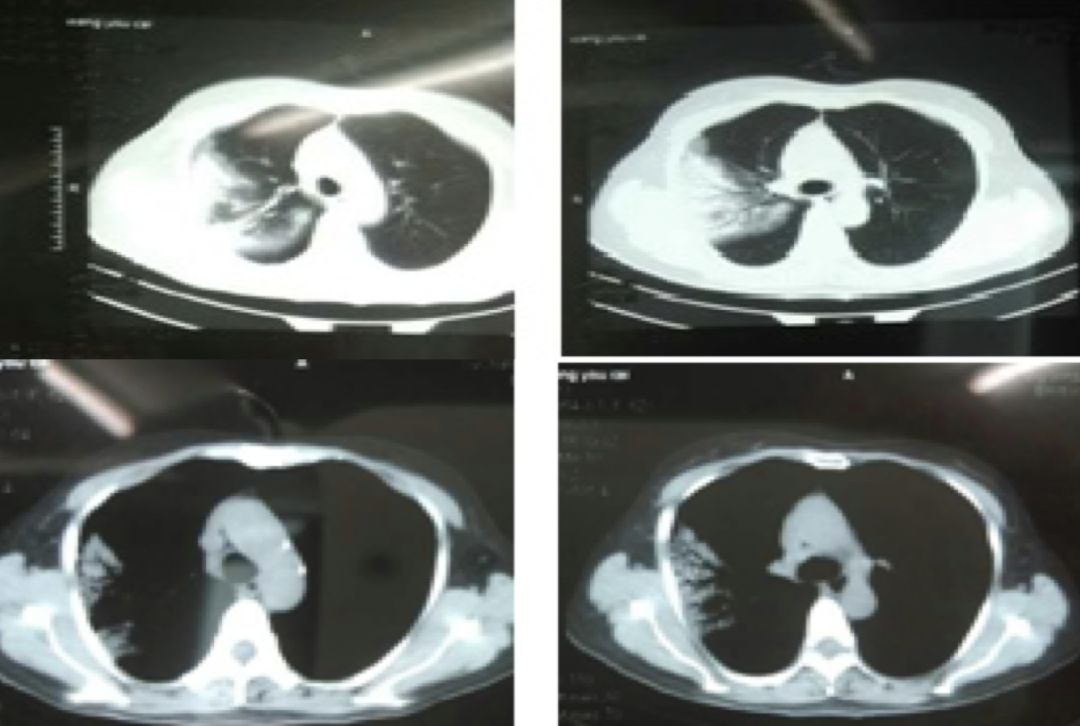

经过抗感染治疗7天,患者体温正常,咳嗽、咳痰好转,间断胸闷,查体 :左上肺语颤稍增强,叩诊浊音,左上肺呼吸音粗,未闻及干、湿罗音。但2017-3-12复查胸部CT,左上肺及右下肺背段病灶无明显吸收。

2017-3-12胸部CT:

2017-3-5胸部CT右上肺大片状高密度影消散,仅留下少许高密度条索影,但左肺上叶后段出现新发病变,但与之前右肺上叶病变影像学特征有所不同,之前三次影像学病灶密度是比较均匀的,此次左肺上叶后段病变,除了实变之外可见类空洞样改变,仍有支气管充气征,周围见细条索影,右下肺背段见类结节影像。

2017-1-23病灶呈楔形改变,还要与急性肺栓塞引起的肺梗死相鉴别,但病变过程及临床检查不支持。影像角度来讲,病灶的游走性是指另一部位发生与该部位同一性质的改变,如另一部位病变与该部位性质有差异,可能是由于疾病的多态性造成的同病异影,也可能是不同性质的病变。